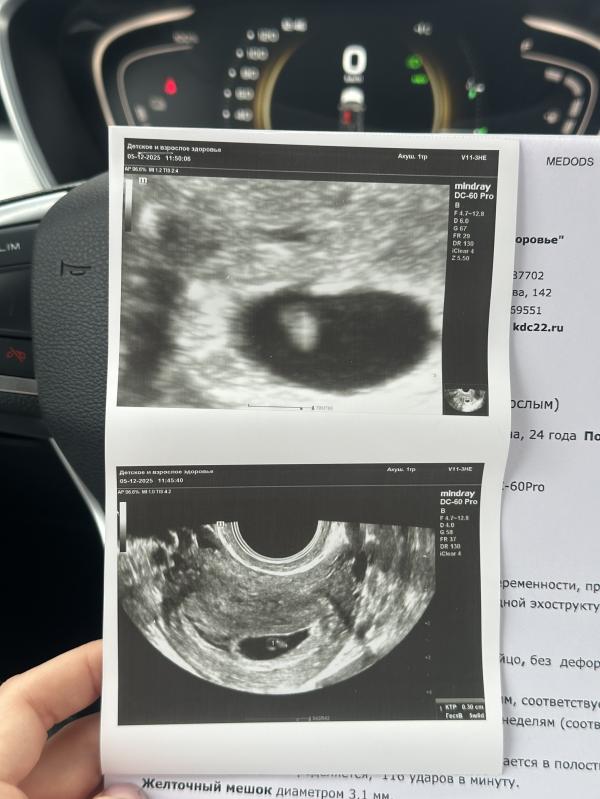

Сегодня мой маточный житель выдал сердцебиение, 5.5 по циклу, по узи поставили 5.6. А вот по моим подсчетом овуляции (и тестам на овул) счет был на 6.0 нед

Испугалась, что отстает, а потом выяснили, что наоборот на сутки быстрее